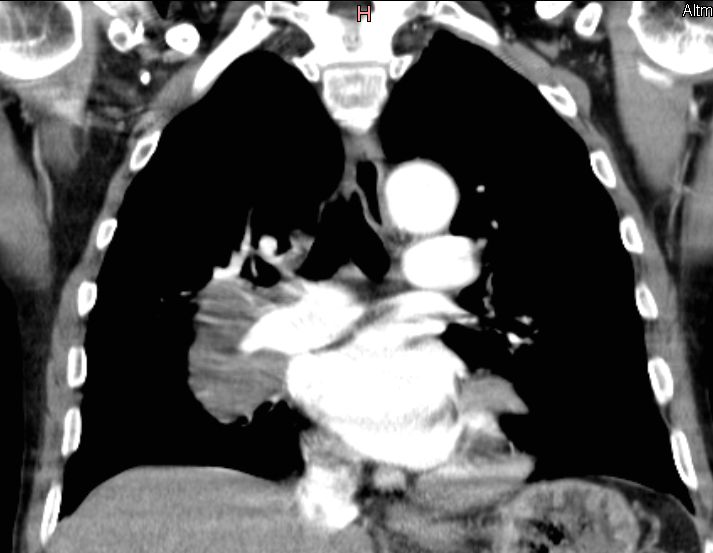

zentrales, kleinzelliges Lungenkarzinom rechter OL mit Infiltration des Mediastinums T4 N3 M1 oss ? 68jährige Patientin im reduzierten AZ und normalen EZ. Unsicherer Gang bei Kreislaufstörungen. Belastungsdyspnoe. Deutliche Leistungsschwäche. Supraklavikulargruben: links frei, rechts auffälliger Tastbefund. ![]() |

![]() |